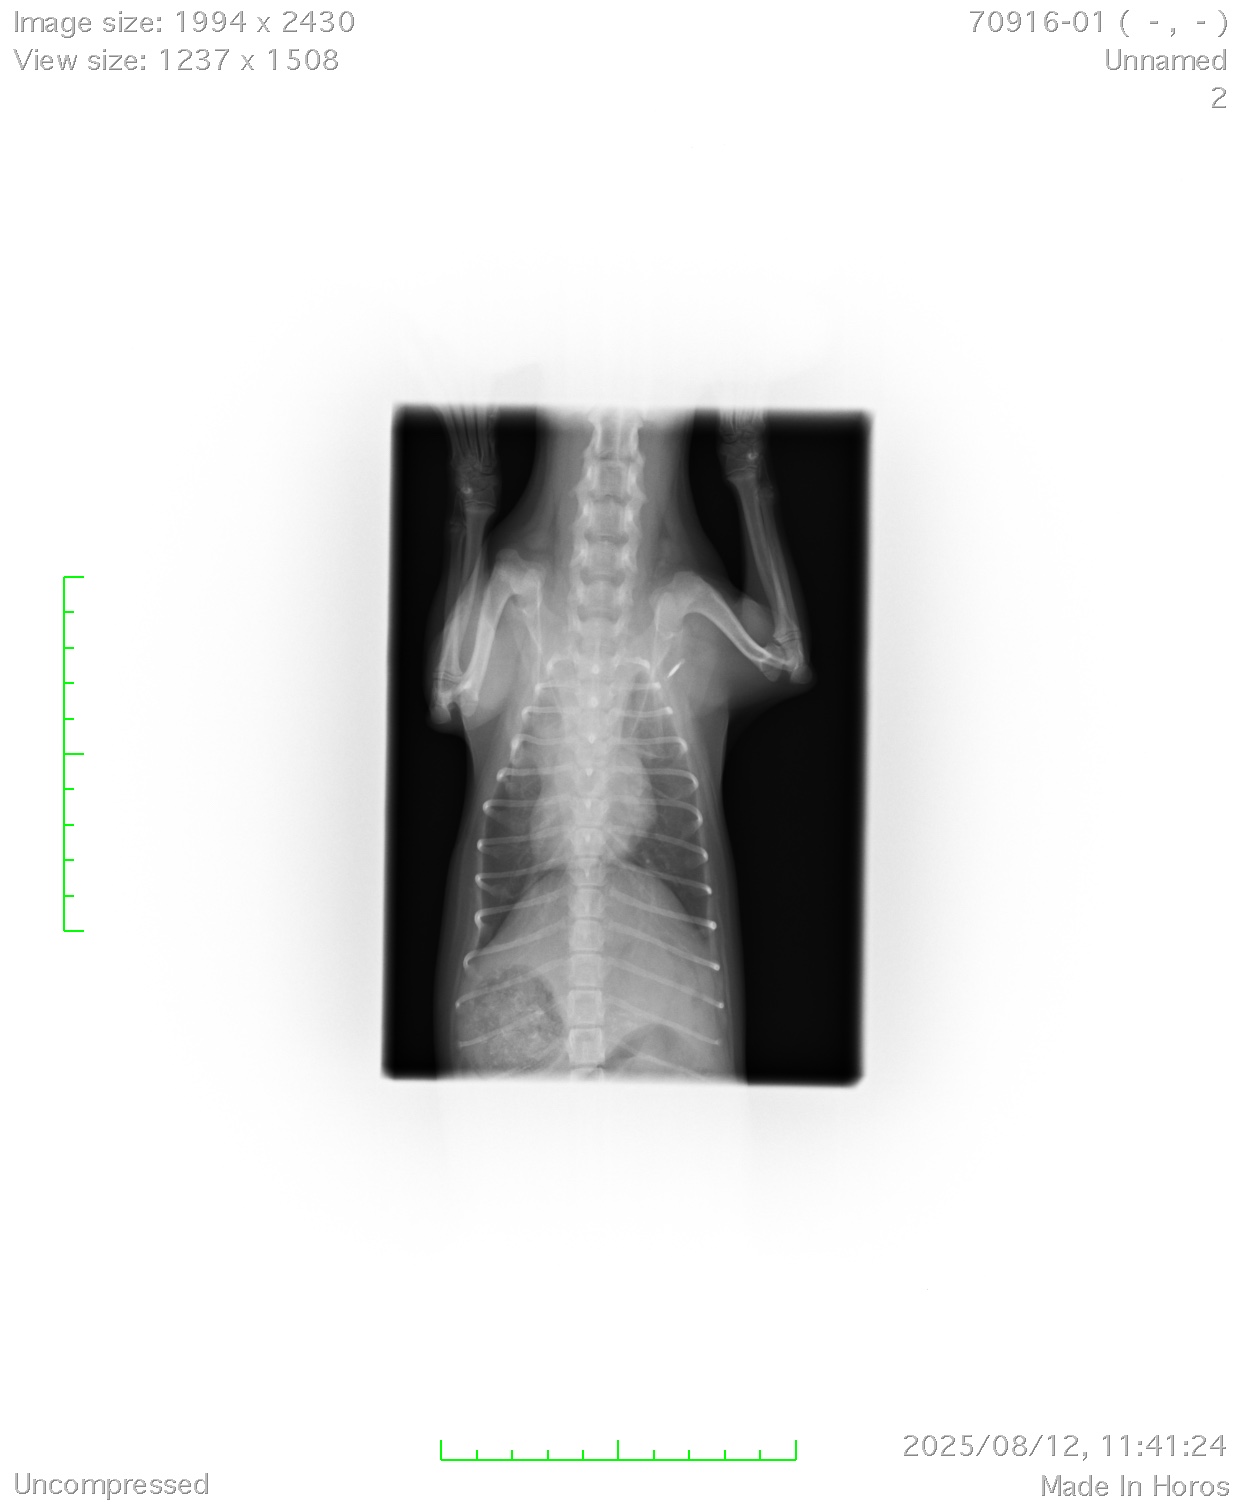

今回は体重がなんと600gと小さいため通常の動物病院では手術はおろか、「開胸」するという大掛かりでリスクの高い手術はほとんどできないと思います。しかし当グループには、体重が小さくても麻酔ができる麻酔の専門家、600g以下でも開胸ができるスペシャルなテクニックを持ったドクターが在籍しており、一般的な動脈管の手術死亡率5〜10%と言われる難易度の手術ですが、現在死亡率0%を維持できております。